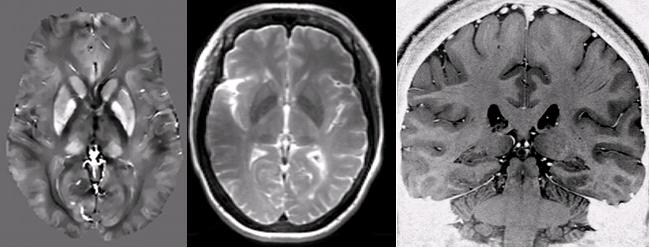

Current Research: Susceptibility and Relaxation and Iron-Sensitive MRI

At the University of Alberta we have a 100% research 4.7 T human MRI system and a 3.0 T Siemens Prisma. These high field instruments offer unique sensitivity to iron through susceptibility and relaxation effects. Iron may be an early marker of neurodegeneration in the brain, as well as being an indicator of changes in deoxygenation and iron storage. It is an extremely important element in the human brain and we are lucky to be sensitized to its measurement when using high field MRI. Our work is finding that iron may be a biomarker of disease state, particularly for multiple sclerosis. More generally, we exploit MRI physics and engineering to enhance imaging methods or "pulse sequences" in new ways to gain more value from MRI. We are interested in susceptibility, structural and relaxation methods, as well as blood vessel imaging and spectroscopy. See my publication section for detailed reading.